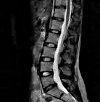

МРТ позвоночника

МРТ позвоночника Современный высокоточный метод сканирования позвоночника, основанный на способности атомов водорода колебаться в переменном магнитном поле. Он используется для выявления травматических поражений, онкологических процессов, воспалительных и дегенеративно-дистрофических заболеваний спинного мозга и позвоночника, а также для контроля эффективности хирургических вмешательств и консервативного лечения данной группы патологий. МРТ позвоночника является наиболее информативной при изучении состояния структур мягких тканей. Не показано наличие металла у пациента.

В современной неврологии МРТ позвоночника назначают при поражениях, изменениях структуры межпозвонковых дисков, воспалительных заболеваниях, сирингомиелии, опухолях позвонков, нервных корешках и спинном мозге. Исследование позвоночного столба методом магнитного резонанса позволяет диагностировать сужение позвоночного канала и выявить его причину, оценить состояние межпозвонковых суставов и паравертебральных тканей; на ранней стадии выявляют участки спинного мозга с недостаточным кровоснабжением. Кроме того, использование томографии имитирует хирургические процедуры и оценивает результаты.

В отличие от рентгенографии и компьютерной томографии позвоночника, магнитно-резонансная томография обеспечивает высококачественное изображение структур мягких тканей. Поэтому применение методики целесообразно при патологии межпозвонковых дисков и связок, для диагностики опухолей, гематом или исследования спинного мозга. Магнитно-резонансная томография позвоночника проводится в поперечной и сагиттальной плоскостях. В сложных диагностических случаях контрастный агент дополнительно вводят для дифференциации опухоли или сосудистой мальформации. Продолжительность обучения составляет около 1 часа.